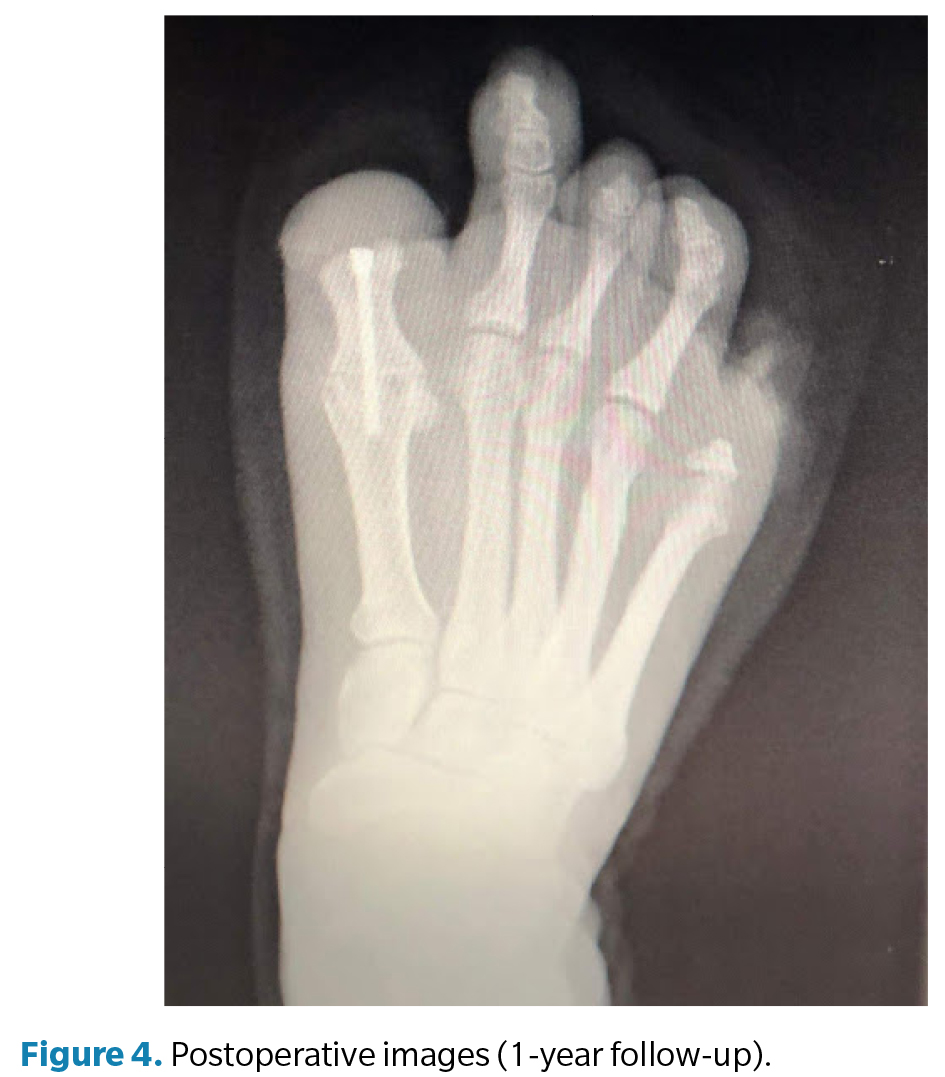

La cirugía (Figura 3) se realizó en marzo de 2022 bajo anestesia regional mediante bloqueo poplíteo posterior con sedación consciente supervisada por anestesiólogo. Se administró profilaxis antibiótica con cefazolina 2 g por vía intravenosa 30 min antes de la incisión y se utilizó torniquete neumático a nivel del tobillo, con presión controlada (a 250 mm Hg) y tiempo de isquemia limitado a 45 min. Se efectuó un abordaje dorsal longitudinal sobre la primera articulación metatarsofalángica, respetando las estructuras neurovasculares. Se identificaron los restos óseos irregulares de la falange proximal y se realizó su resección completa, seguida de remodelado de los márgenes óseos hasta obtener superficies regulares y viables. Posteriormente, se prepararon las superficies articulares de la primera metatarsofalángica mediante fresado y curetaje hasta lograr una base sangrante adecuada para la artrodesis. La posición de fusión se determinó intraoperatoriamente mediante pruebas de carga, fijando el hallux en aproximadamente 10° de dorsiflexión respecto al plano del suelo, con el fin de optimizar la propulsión y evitar la sobrecarga plantar en el muñón residual. La fijación definitiva se realizó con 1 tornillo canulado tipo Herbert, verificándose estabilidad intraoperatoria y correcta alineación mediante fluoroscopia (Figura 4). El procedimiento concluyó sin incidencias, con hemostasia cuidadosa y cierre por planos.

El postoperatorio incluyó curas secas periódicas y seguimiento funcional progresivo. A los 3 meses de la intervención se constató resolución completa del dolor y mejoría significativa en la calidad de la marcha. A los 6 meses la paciente presentó recuperación funcional satisfactoria, por lo que se procedió al alta médica temporal. Posteriormente se confeccionaron prótesis digitales de silicona personalizadas para ambos pies, destinadas a mejorar la simetría podológica, la distribución de cargas y la aceptación psicosocial. En el seguimiento a los 12 meses, la paciente se mantenía asintomática, con consolidación radiográfica completa de la artrodesis, alineación correcta del primer radio y marcha estable sin limitaciones, confirmando el éxito funcional del procedimiento.

Finalmente, debe subrayarse que el seguimiento a largo plazo constituye un elemento esencial para valorar los resultados de este tipo de intervenciones. En este caso, el control a 12 meses mostró consolidación completa de la artrodesis, ausencia de dolor y restitución de la marcha fisiológica, confirmando la eficacia del abordaje.